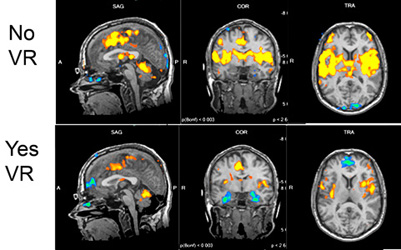

Research has found that virtual reality can help people resist pain for longer periods of time, and even more so when you add sound. Using an Oculus developer headset, researchers from York St. John University in the U.K. had a group hold their hands in ice water and time how long they could last.

While dipping one hand into ice water, the subjects played a racing game with the sound turned on. Subjects lasted an average of 79 seconds before pulling their hand out.

Next, they did the same test except without sound to go along with the immersive visuals. Researchers found that, on average, people were able to last 56 seconds in the ice water when viewing only VR images.

When the researchers did the ice water test without using VR equipment, then found that subjects were only able to last an average of 30 seconds. Of course, this does raise questions about, well, simply being distracted by anything when you are undergoing physical duress. What connections can be made between pain tolerance and normal gaming or maybe watching a movie? How does virtual reality (indeed, does virtual reality) stand apart?